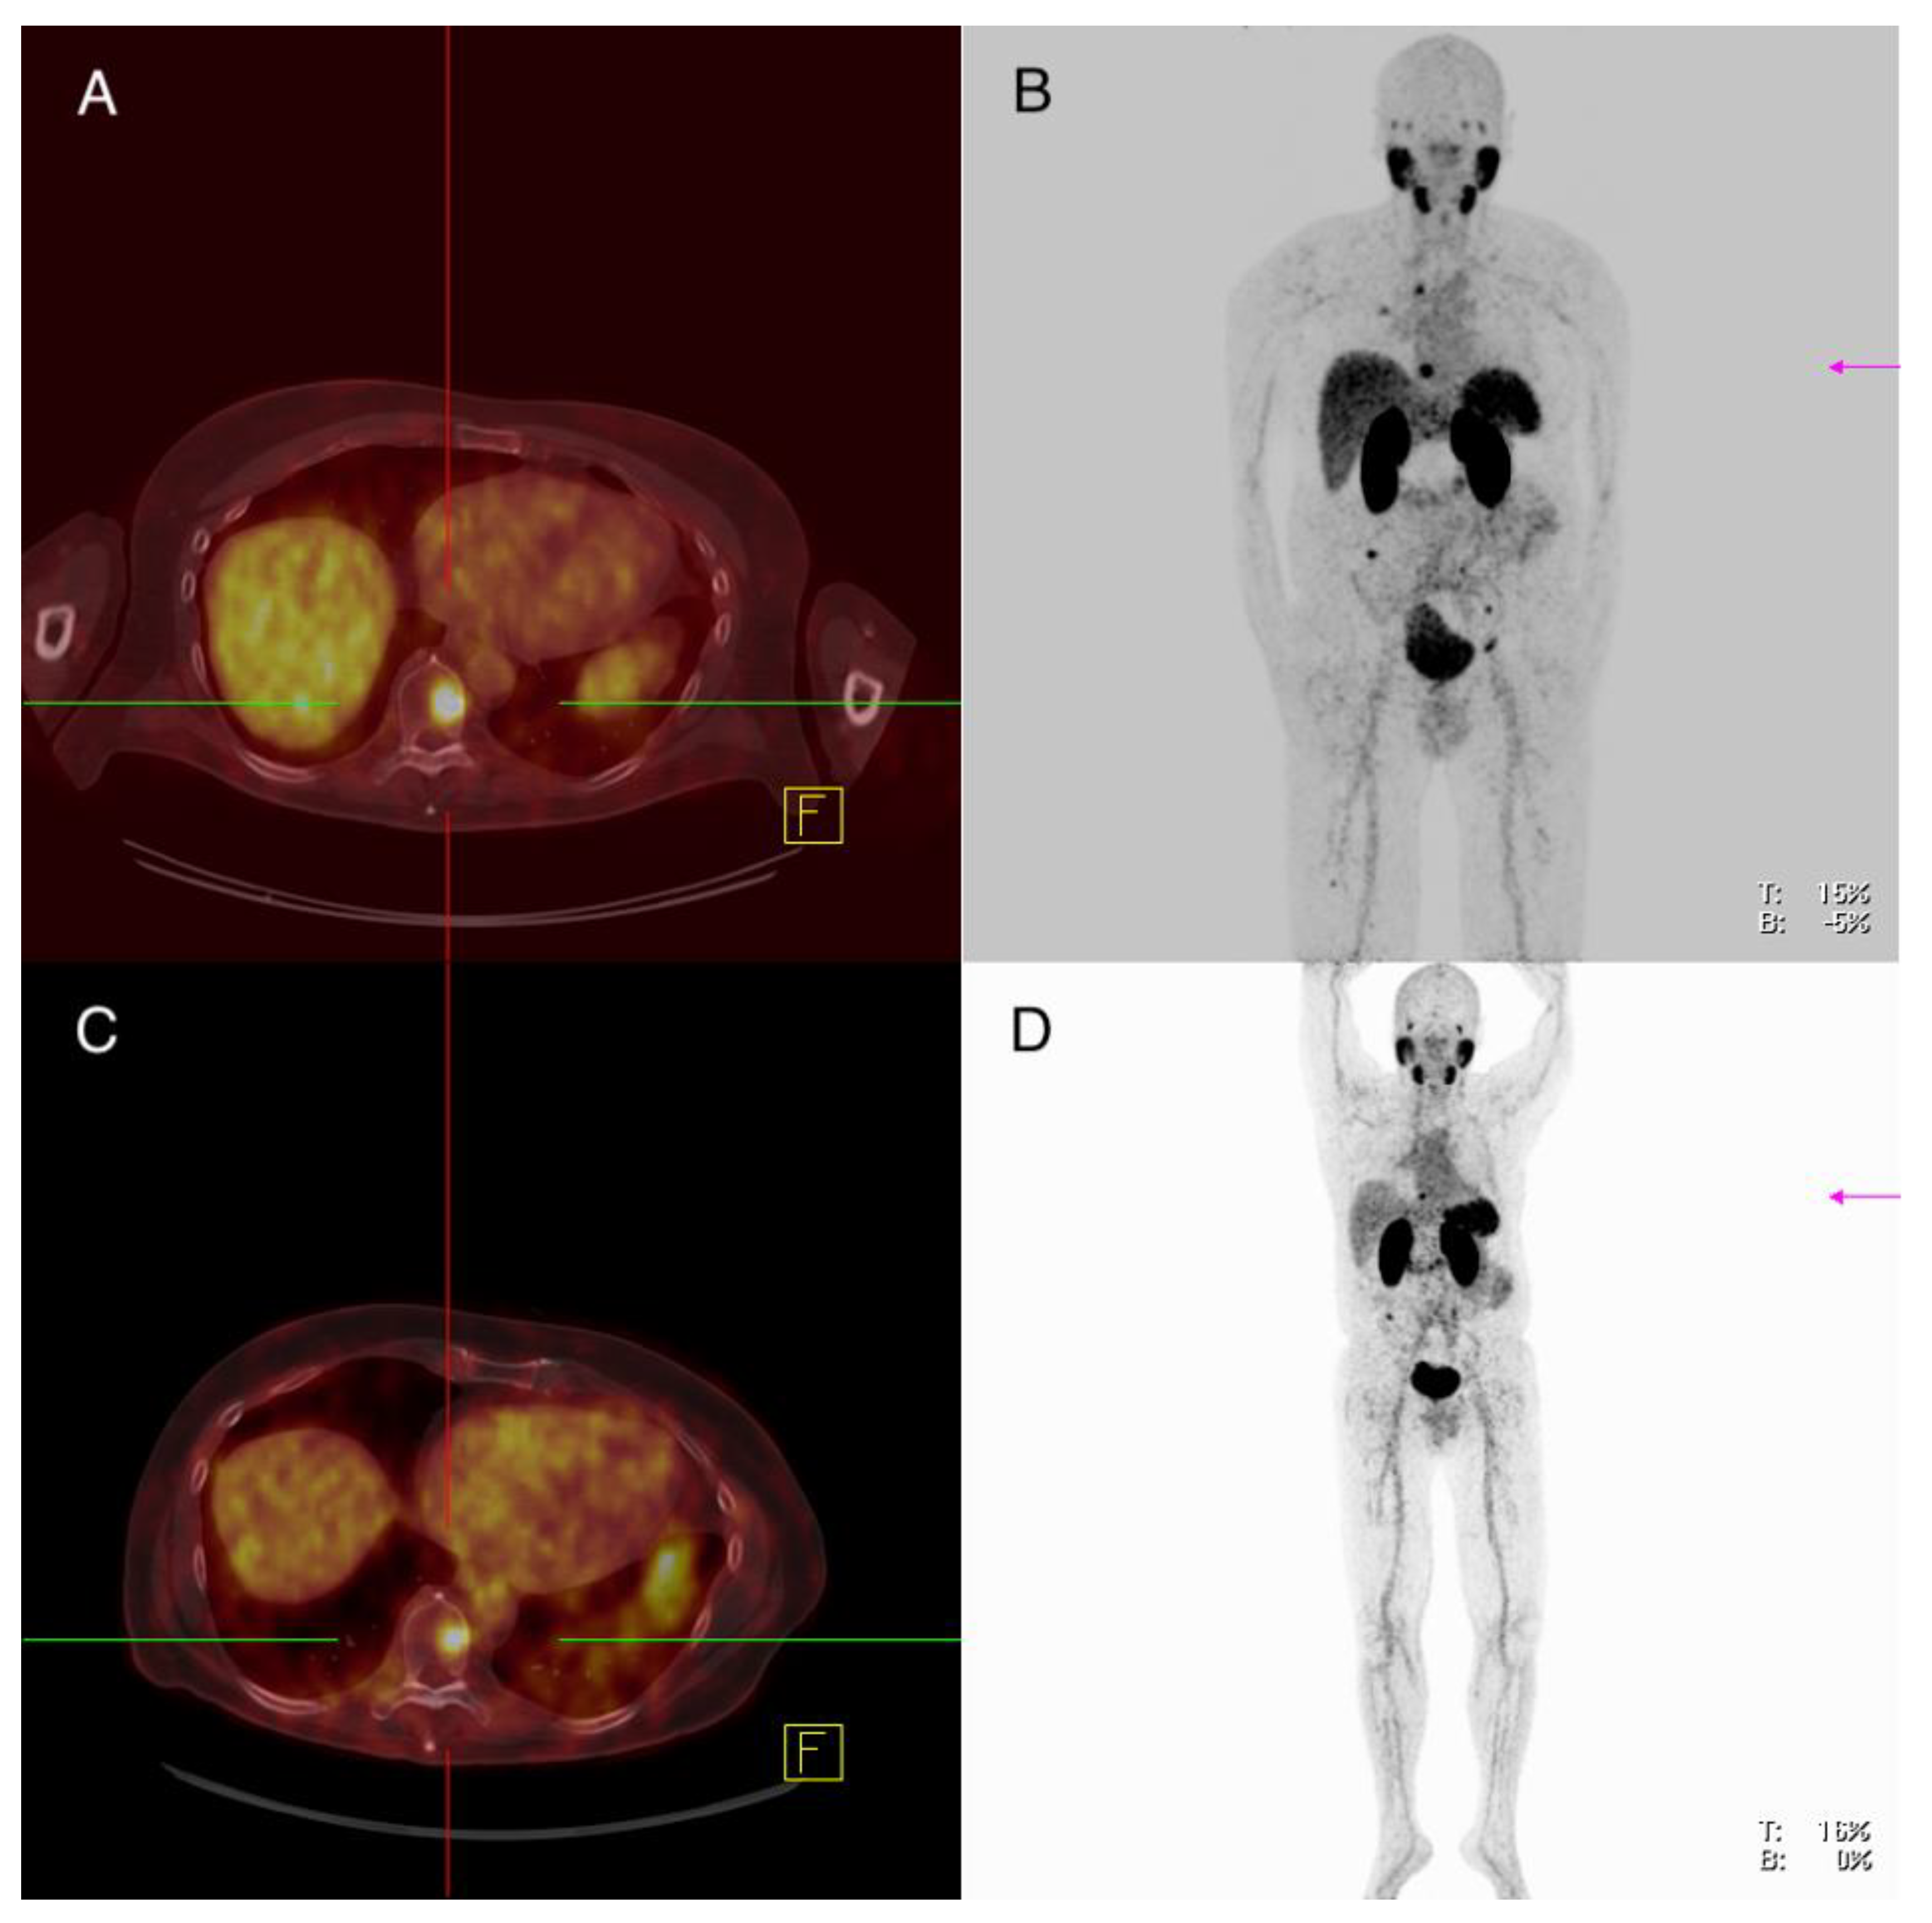

3.3.3. Setting No. 3—68Ga-PSMA-PET/CT Clearly Positive, Theranostic Approach

Patient 8: Male, PDTC, 59 Years Old at Time of Diagnosis

| 8 | M | 59 | 2015 | PDTC | pT0 cN0 M1 | IVB | Surgery of the thyroid gland (2011) Surgery of vertebral metastasis (2015) Residual thyroidectomy without tumor detection (2015) Radioiodine therapy (14,9 GBq I-131) (2015) Two cycles of Lutetium-177-PSMA therapy (cumulativ 13,7 GBq) (2017) mKI therapy (Lenvatinib) (2018) COSMIC study 2 inclusion (2020) |

| 8 | 2015 | PSMA: 2016 FDG: 2016 | 81 | OM 4 (n = 4) 1.25 (0 *–1.6) | 2.3 (1.2–2.7) | 5.55 (2.9–9.0) | No tissue sample of this patient was available | |